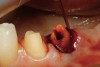

Figure 13  Preoperative view of a fixed partial denture that spanned anteriorly from tooth No. 18 to tooth No. 21. There was a minor biologic width encroachment on the distal aspect of the anterior abutment, tooth No. 21. The anterior abutment also had recurrent facial decay apical to the restorative margin and a lack of attached gingiva on the facial aspect.

Figure 13

Figure 15  After removal of the defective restoration, it can be seen clinically that the margin of the preparation on the distal of tooth No. 21 was extremely subgingival. The surrounding periodontium was inflamed and hemorrhagic. The laser was used to perform apical repositioning of the bony crest using a closed-flap technique.

Figure 15